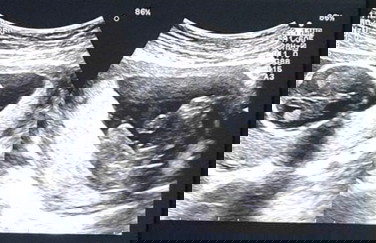

Can you help me guess the gender of my baby?? I'm at week 16 now.

I think boy.